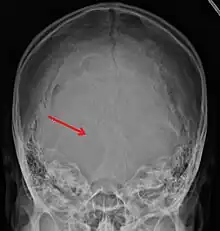

Undisplaced occipital skull fracture as seen on plain Xray

Linear skull fractures are breaks in the bone that transverse the full thickness of the skull from the outer to inner table. They are usually fairly straight with no bone displacement. The common cause of injury is blunt force trauma where the impact energy transferred over a wide area of the skull.

Linear skull fractures are usually of little clinical significance unless they parallel in close proximity or transverse a suture, or they involve a venous sinus groove or vascular channel. The resulting complications may include suture diastasis, venous sinus thrombosis, and epidural hematoma. In young children, although rare, the possibility exists of developing a growing skull fracture especially if the fracture occurs in the parietal bone.[2]